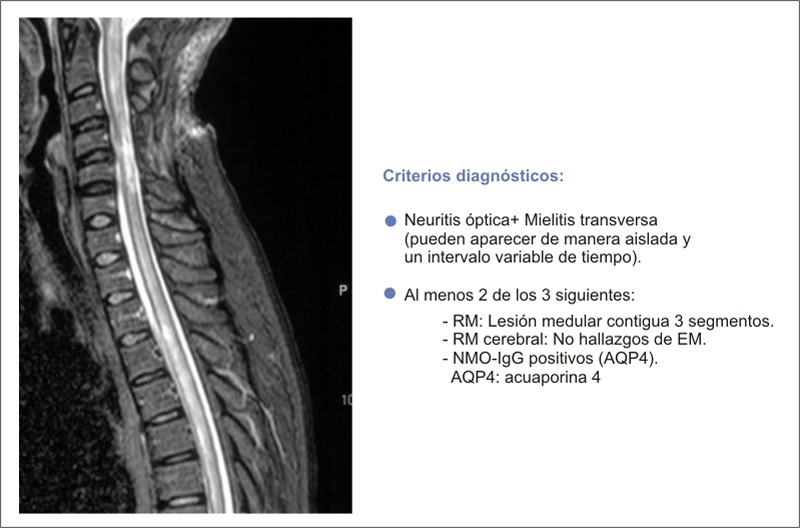

- Escotoma juncional. Una afectación difusa del campo visual (CV) de un ojo asociado a un escotoma en el CV temporal superior del ojo contralateral indica lesión en la unión del nervio óptico con el quiasma (neuropatía óptica distal o síndrome del quiasma anterior) (Figura 11).

Figura 11. Depresión generalizada ojo izquierdo y escotoma temporal superior ojo derecho, indica lesión en unión nervio óptico con quiasma

- Defectos retroquiasmáticos. La alteración campimétrica habitual es la hemianopsia homónima. Sus características y asociación a otras anomalías exploratorias permiten apuntar a la localización de la lesión en la RM:

- Síndrome de cintilla óptica. Asocia una hemianopsia homónima, que suele ser poco congruente con una atrofia óptica en banda yDPAR contralateral y atrofia óptica temporal homolateral a la cintilla afecta (Figura 13).

Figura 13. Hemianopsia homónima izquierda secundaria a comprensión de cintilla óptica derecha por malformación arteriovenosa. Asociaba DPAR izquierdo y atrofia óptica difusa ojo derecho y en banda ojo izquierdo